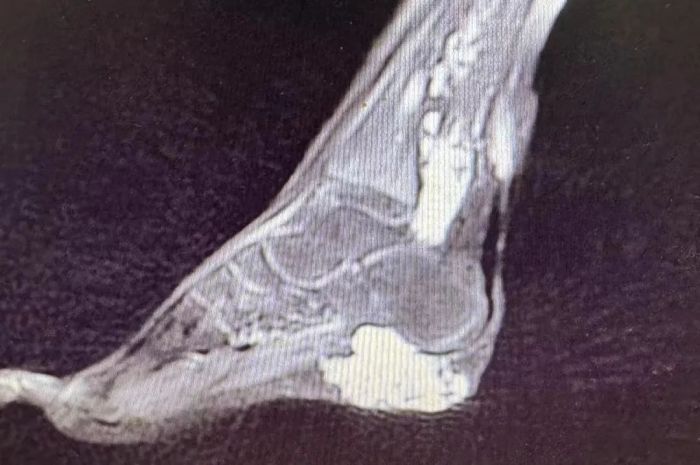

无独有偶,11岁的小邓(化名)随着年龄生长,膝盖和脚底存在不同程度的肿胀、青紫现象,就像一条条正在蠕动的“虫子”。医生检查后明确诊断为左下肢静脉畸形。家长带着孩子曾多次在广州某医院做治疗,但是效果欠佳,而且在外地诊治花费较大。

得知桂林市妇幼保健院一直开展有血管畸形治疗业务,于是前来求助。经过医患双方讨论,最终决定开展局部注射硬化治疗。经两次硬化治疗后,小邓下肢酸胀、疼痛感明显好转,从外观看曲张的静脉明显减少,家属对治疗效果比较满意,目前已出院。

静脉畸形是一种先天性的血管发育异常,表现为皮肤或黏膜下的蓝色或紫色团块,常出现在头颈部、四肢或口腔内。它由一团杂乱增生的静脉血管构成,并非肿瘤,但可能随年龄增长而扩大,导致疼痛、肿胀甚至影响器官功能。临床上通过超声、磁共振(MRI)等检查可明确诊断,典型特征包括“体位试验阳性”(按压后肿块缩小、松开后复膨)。